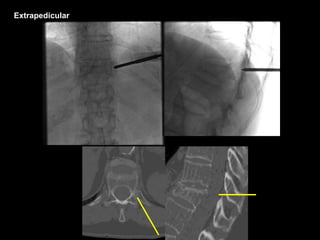

Extrapedicular

Biopsy

Oblique View

Balloon Tamps

Cement

Wong W, MathisJM. Vertebroplasty and kyphoplasty: techniques for avoiding complications and pitfalls. Neurosurg Focus 18 (3):E2, 2005. Extrapedicular